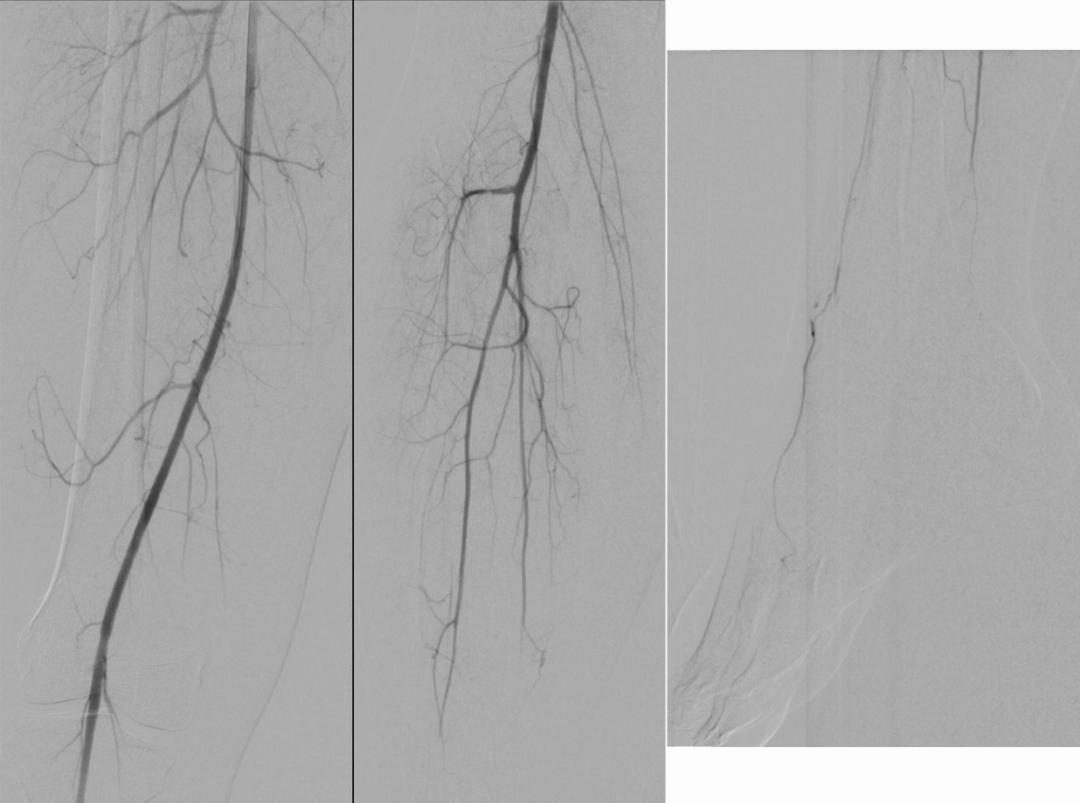

患者接受了紧急血管造影,发现左下肢腘动脉远段、胫前动脉和胫腓干有多发栓子(图2)。通过抽吸取栓术从左下肢抽出了白色胶状物,显微镜下标本显示为黏液瘤的细胞结构和基质,术后左下肢灌注恢复。右下肢血管造影发现踝部有小栓子,但侧支循环和足底弓灌注存在,未采取干预措施(图3)。

图3. 右下肢血管造影

发现踝部有小栓子,但侧支循环和足底弓灌注存在,未采取干预措施